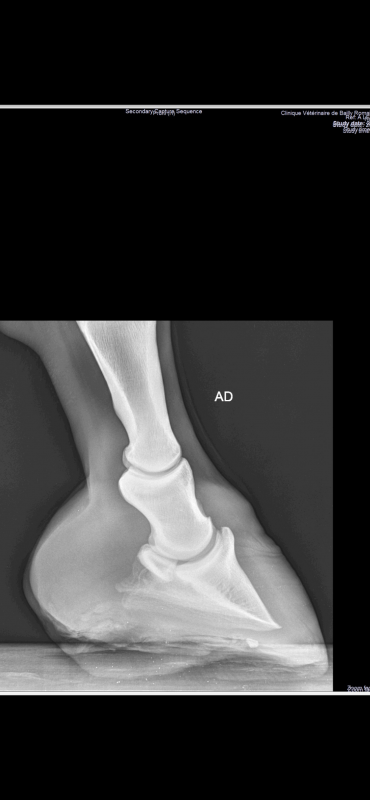

Voilà les dernières radios de ma jument. Ainsi que ses pieds actuellement :

Les pieds de ta jument sont pas beaux du tout. Les talons sont serrés et hauts. Il y a peut être 1cm de talons en trop et les barres sont très orientées vers la verticale, elles empêchent complètement la distorsion de l'arrière du pied.